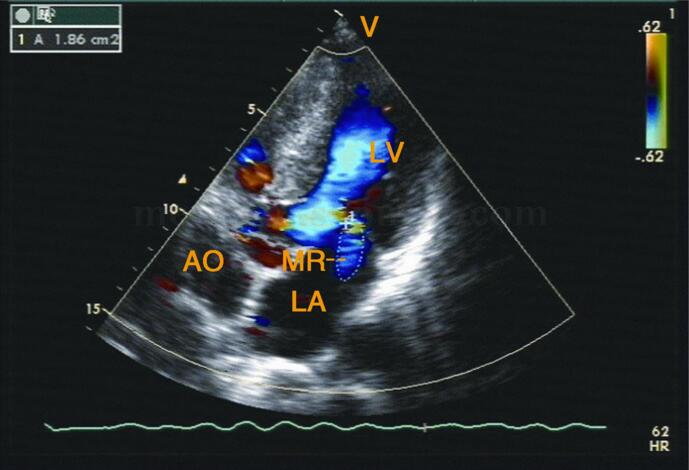

3﹒彩色多普勒超声

(2)非梗阻者:左室流出道收缩期充满蓝色血流(图2‐1‐208)。

图2‐1‐208 非梗阻者左室流出道收缩期充满蓝色血流,左房内见蓝色二尖瓣反流束

(3)常合并不同程度的二尖瓣反流。